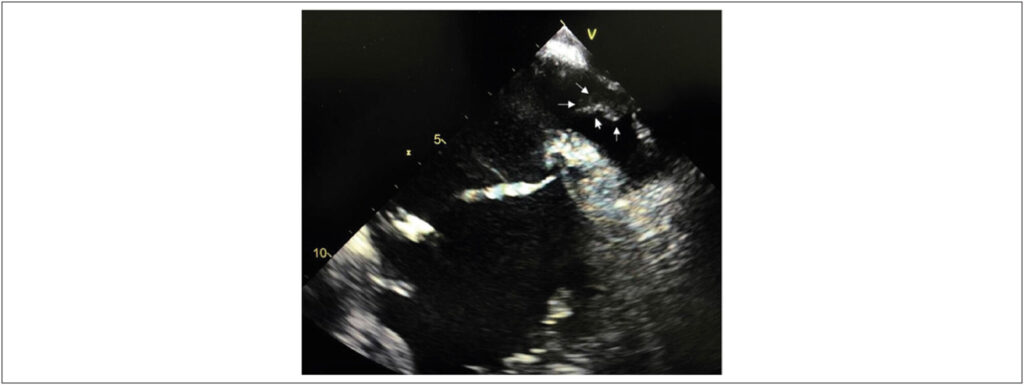

TEE is considered the gold standard test to detect LAA thrombi., With the incorporation of heart CT-angio into clinical practice, the diagnosis of a “false” thrombus, called pseudo-thrombus, in the LAA has become more frequent and is explained by contrast filling failure due to reduced flow velocity in the LAA trabeculae. The recent use of specific CT-angio protocols to evaluate thrombi and late imaging capture has significantly improved its sensitivity and specificity, which reaches near 100% in some series,, thus becoming a less invasive option than TEE. It has been widely used in preoperative catheter ablation to treat AF or LAA percutaneous occlusions.

In this case, it is noteworthy that the diagnosis of pseudo-thrombus by TEE corresponded to an extracardiac metallic structure (stent) artefact closely related to the LAA but only identified on the cardiac CT-angio and relevant in the patient’s treatment.